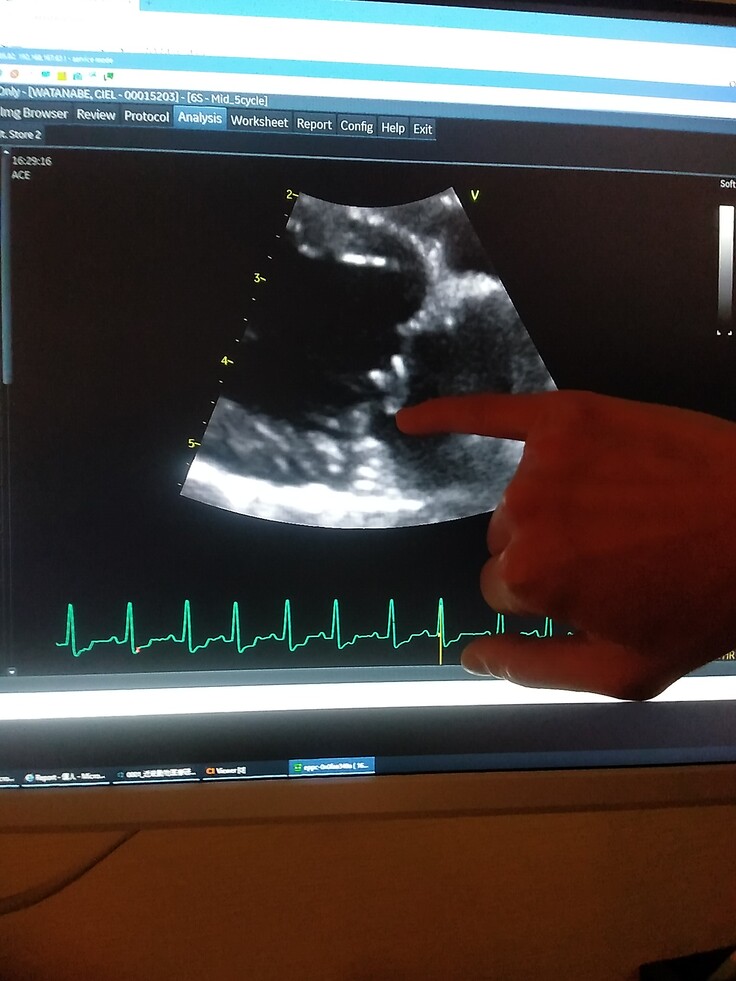

Cielの弁膜はブチブチに切れている状態で、かなり逆流もある。

※血液が逆流しています。

※3月9日、二次診療で獣医師から検査結果を説明して頂きました。